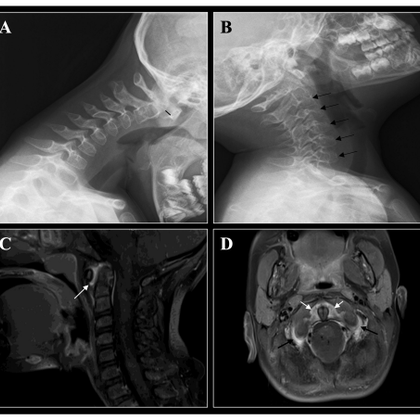

Nueva publicación en Pediatric Rheumatology Cervical spine arthritis as initial manifestation in Juvenile Idiopathic Arthritis 🔗 https://t.co/9rLWkwqBkO La cervicalgia persistente puede ser la primera manifestación de la AIJ. Reconocerla es clave! @MCorbeto @vallhebron

Contena de participar en este estudio publicado en Pediatric Rheumatology, un esfuerzo colaborativo para subrayar la importancia de la detección temprana de la AIJ en manifestaciones poco habituales como la cervicalgia.